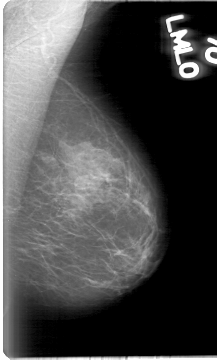

D_4015_1.RIGHT_CC

RIGHT_CC LINES 5341 PIXELS_PER_LINE 2926 BITS_PER_PIXEL 12 RESOLUTION 43.5 OVERLAY